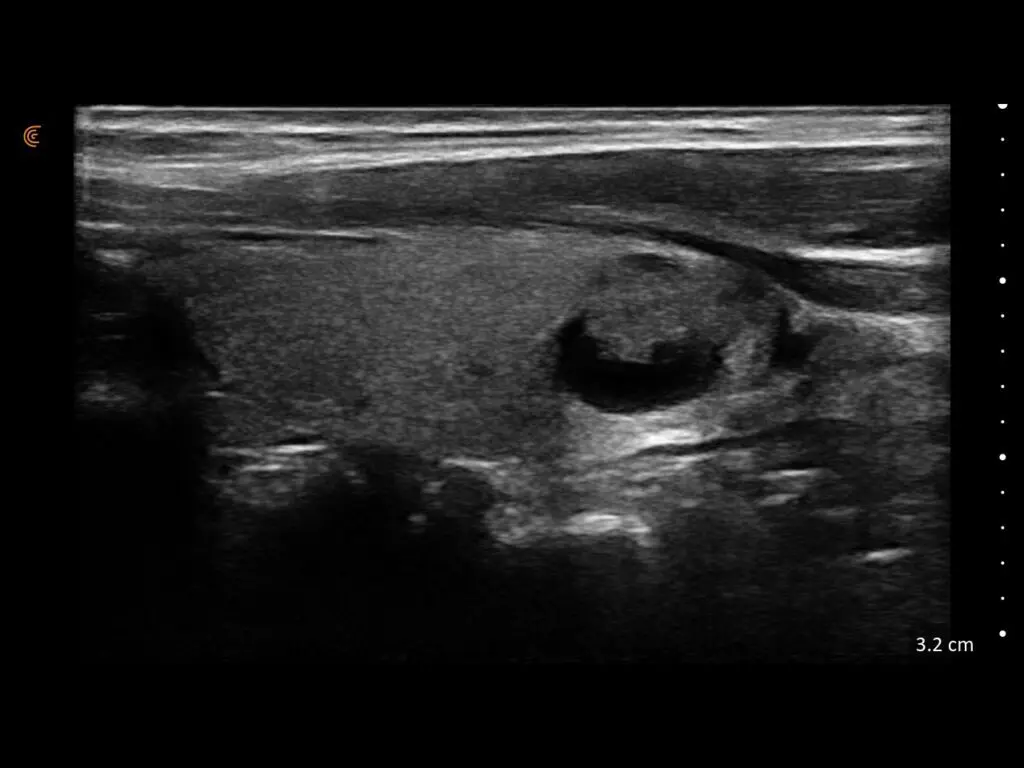

ProbeFix Dynamic is a new device that enables high-quality ultrasound measurements during dynamic exercise by keeping an ultrasound probe in place, allowing for muscle monitoring during intense movement and creating new research possibilities in muscle imaging.